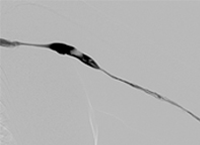

Case CLI with Right Foot Ulcer Thrombectomy pre-procedure arteriogram.

Arteriogram of posterior and anterior tibial post-CDT

PT and AT remained occluded following overnight CDT infusion of lytic